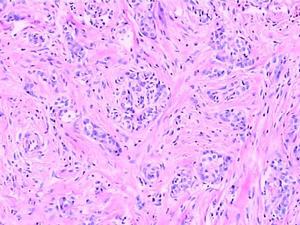

染色的目的是使細胞組織內的不同結構呈現不同的顏色以便於觀察。未經染色的細胞組織其折光率相似,不易辨認。經染色可顯示細胞內不同的細胞器及內含物以及不同類型的細胞組織。染色劑種類繁多,應根據觀察要求及研究內容採用不同的染色劑及染色方法,還要注意選用適宜的固定劑才能取得滿意的結果。經典的蘇木精(Hematoxylin)和伊紅(曙紅,Eosin)染色法是組織學標本及病理切片標本的常規染色,簡稱HE染色。經HE染色後,細胞核被蘇木精染成紫藍色,多數細胞質及非細胞成分被伊紅染成粉紅色。由於蘇木精是帶陽離子的染料,染液呈鹼性,核內染色質及胞質核心糖體等物質對這種染料有親和性,稱嗜鹼性;而帶陰離子的染料伊紅配製的染液呈酸性,對這種染料的親和性,稱嗜酸性。有時不同的組織結構還需要用特殊的染料及染色方法加以顯示,稱特殊染色。有些細胞組織經硝酸銀浸潤後,可使溶液中銀離子還原成金屬銀或銀粒附著在細胞組織上,呈棕黑色,這種性質稱親銀性,而有些細胞組織本身不能使硝酸銀的銀離子還原成金屬銀,還需加還原劑才能將銀離子還原,稱嗜銀性。